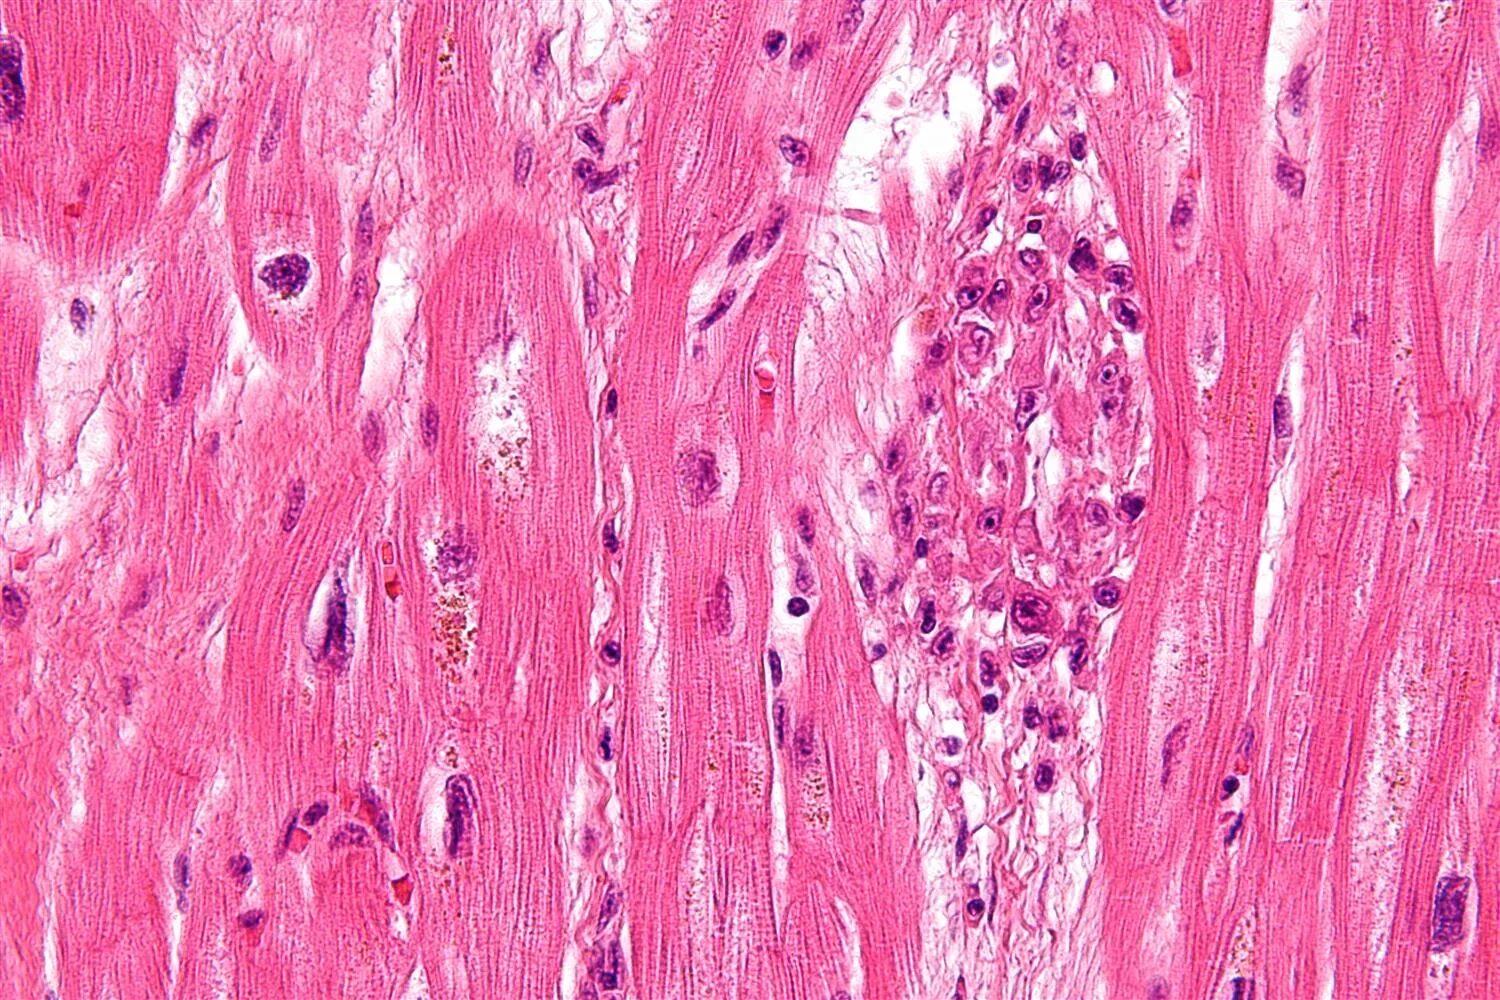

Микроскопическое строение тканей человека